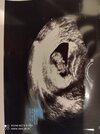

Hej mamusie. Powiedzcie mi czy tutaj jest jedenczy dwa pęcherzyki ? Z pierwszej wizyty w 5 tygodniu i drugie usgz 6 tygodnia. Ginekolog nic nie wspomniał żesą dwa za to przepisał duphaston i luteine. Czy tylko ja tam widzę dwa ?

chyba trochę za duza ta odległość. Może to jakiś krwiaczek ja tez miałam czarna plamę na USG nad pecherzykiem właściwym właśnie w 5t to lekarz mówił że nie wie co to może będę z tego krwawić. Ale minęło i na razie cisza.

nie znam się ale może to krwiaczek ? Z tego co pamietam na moim usg wyglądał podobnie do pęcherzyka 🙈 przynajmniej dla mnie 😉

Myśle ze lekarz powiedziałby Ci o drugim pęcherzyku, to dość istotne 😉